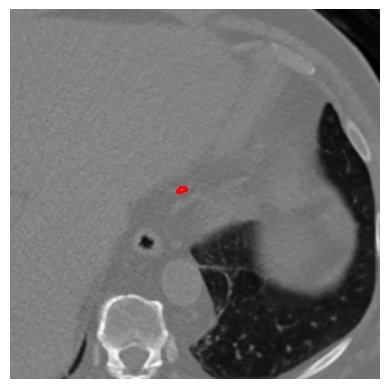

Refer to caption

(a) Confusion Matrix for CAC class prediction using U-NET on the Test Dataset

(b) Confusion matrix for CAC class prediction using U-NET on the annotated dataset, highlighting classification accuracy with annotated slices only.

Figure 7: CAC class predictions for each patient in the test dataset using U-NET.

The U-NET architecture performs well in identifying high risk calcification areas but encounters challenges with smaller calcified regions in CT slices. The lack of annotations for many CT slices often leads the model to incorrectly segment unannotated areas, significantly impacting F1-scores due to potential mislabeling. The CAC scoring results produced by the U-NET architecture are shown in Figure 7(a), while Figure 7(b) illustrates the CAC classification results using the annotated dataset. The discrepancies between these results indicate that CT slices without calcified areas have a negative impact on the overall classification performance.